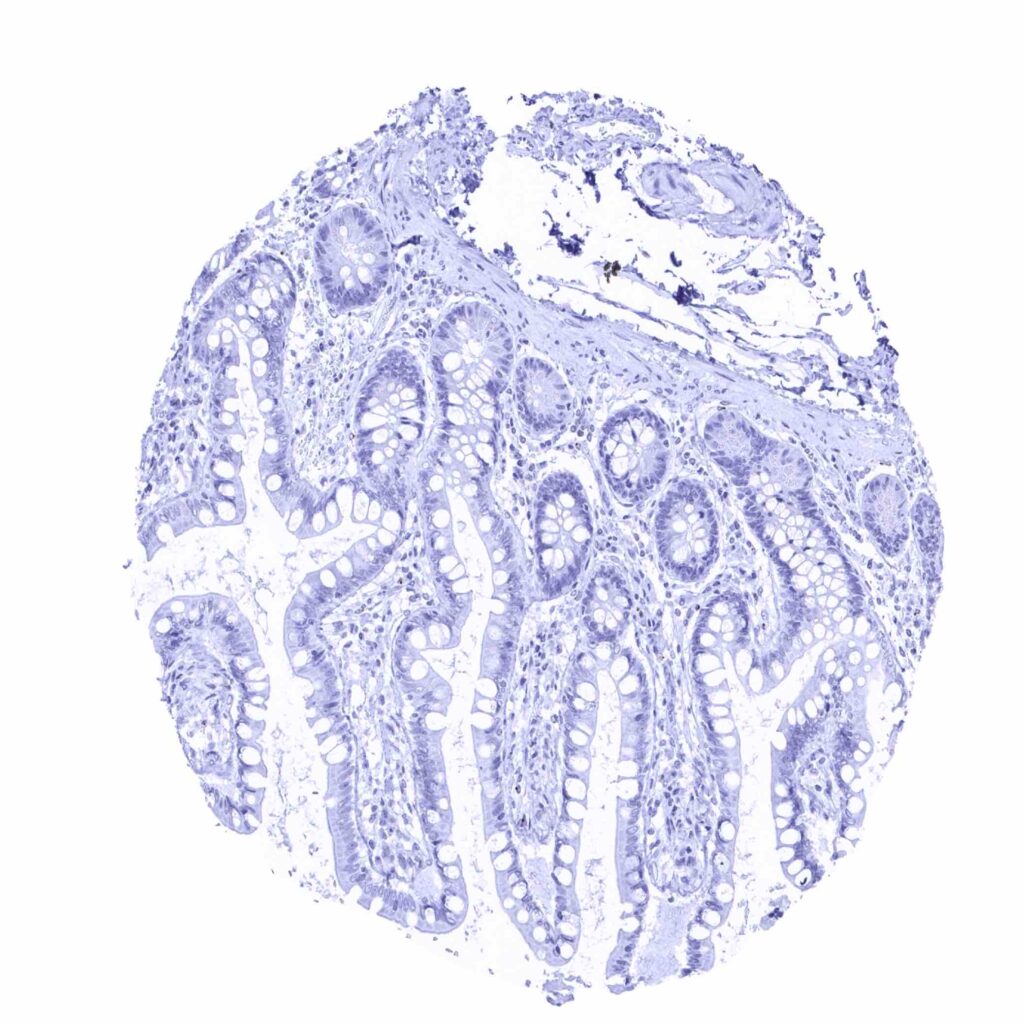

Appendix, mucosa – Prostein staining is lacking